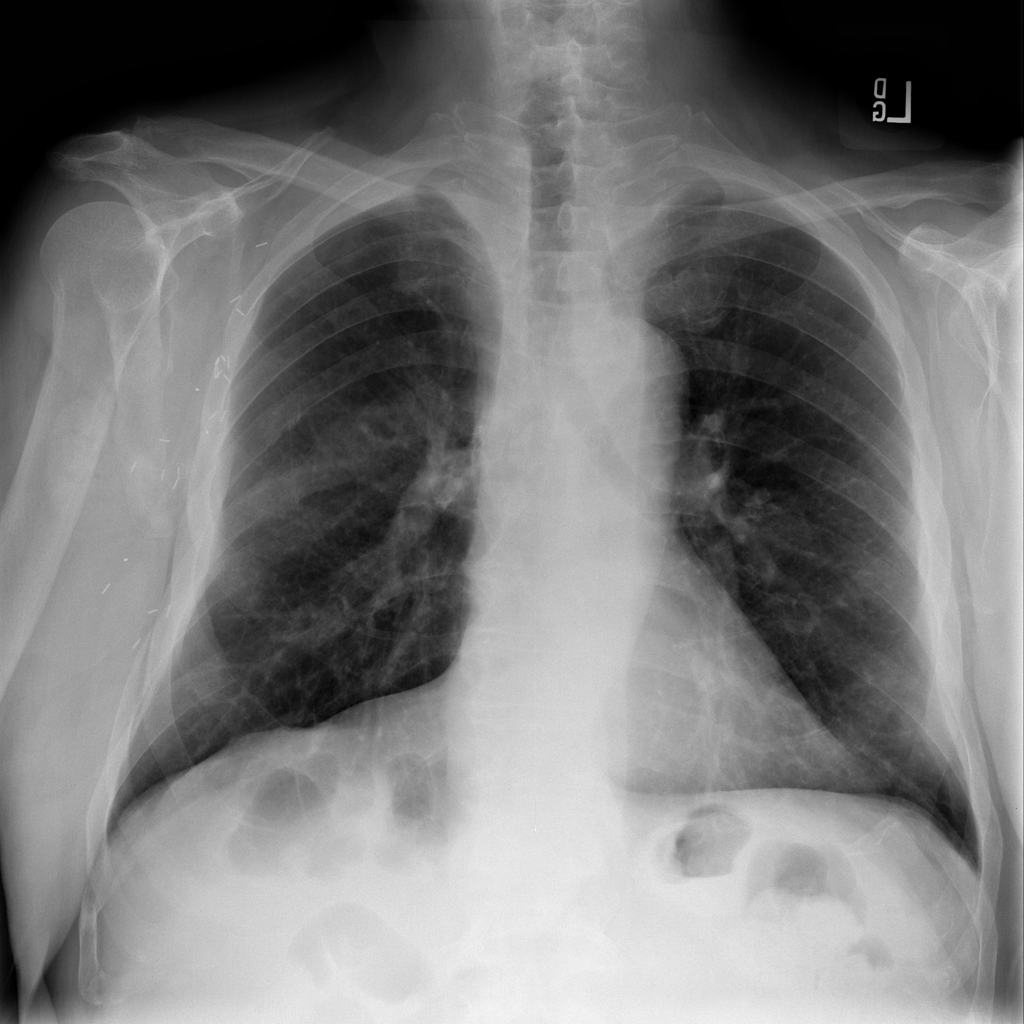

Nodule

A nodule is a small rounded opacity in the lung or chest field. It is a descriptive imaging finding that can be benign or more concerning depending on size, appearance, and context.

Showing up to 90 reference images for Nodule.

PAT-F3E7 · IMG-002Nodule

PAT-F3E7 · IMG-002

PA